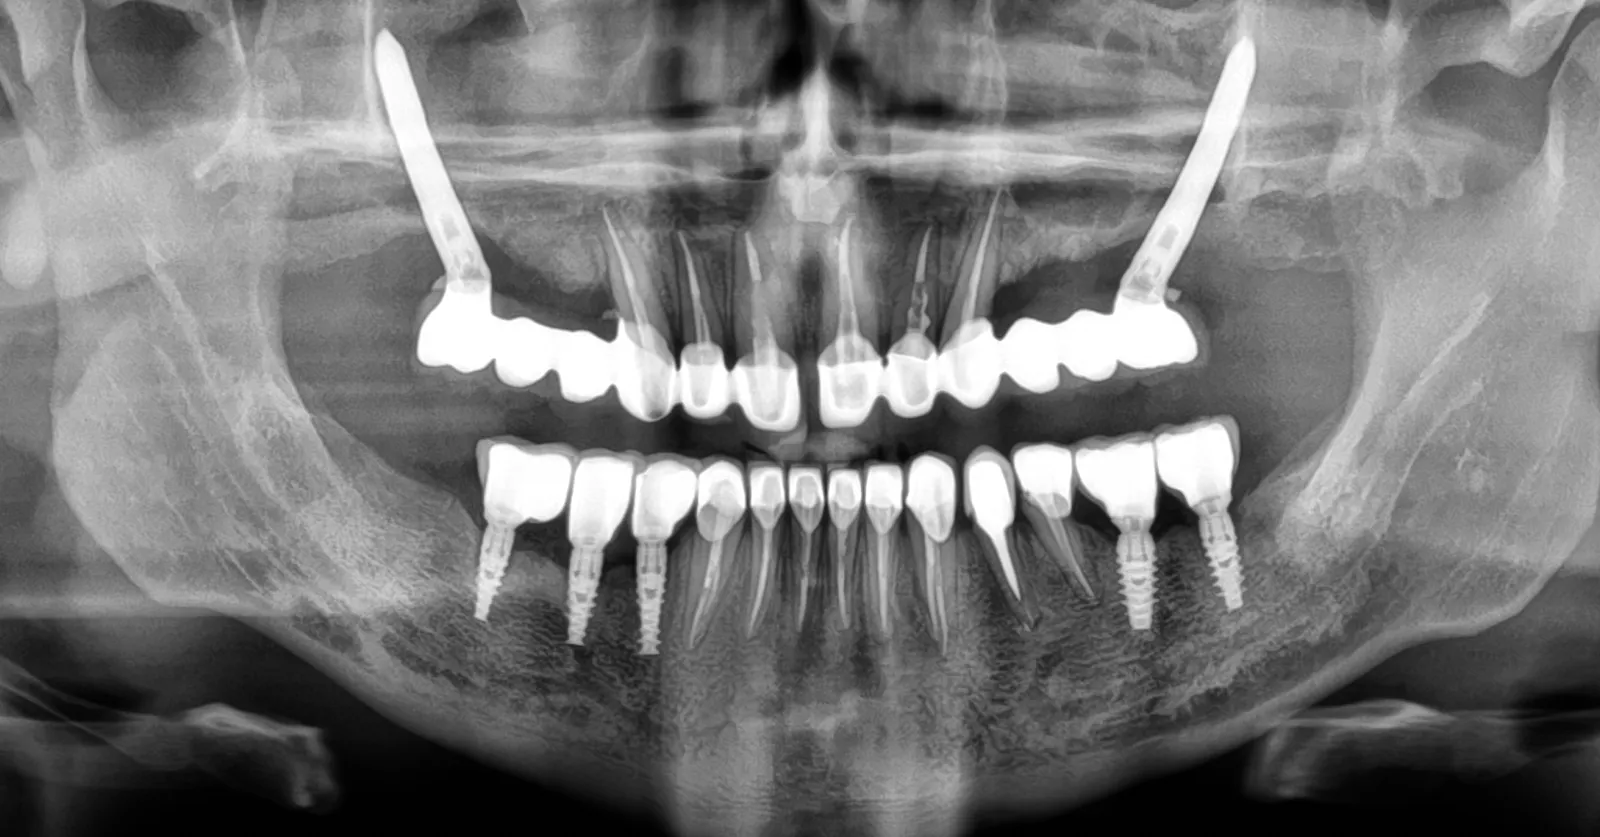

Implanty zygomatyczne nazywane są także implantami jarzmowymi. Zanim odpowiemy na pytanie, implanty zygozmatyczne – czym są – warto wspomnieć, że nasza klinika – a konkretniej chirurg implantolog dr Radosław Witkowski – jako jedna z pierwszych w Polsce zaczęła stosować to rozwiązanie do leczenia pacjentów. Implanty zygomatyczne to długie implanty, wprowadzane w znieczuleniu ogólnym w odcinkach bocznych, w okolicę łuku jarzmowego szczęki.

Implanty zygomatyczne są zalecane szczególnie u osób, które cierpią na bezzębie całkowite w szczęce lub inne, trudne warunki kostne. Tego rodzaju implanty, nazywane jarzmowymi, to alternatywa dla bardziej skomplikowanych metod leczenia – np. z użyciem przeszczepów kości własnej pacjenta. Implanty zygomatyczne gwarantują pełną odbudowę protetyczną nawet w bardzo skomplikowanych lub trudnych przypadkach. Taki zabieg jest szybszy, mniej bolesny i bardziej bezpieczny, z punktu widzenia pacjenta stanowi o jego przewadze np. nad przeszczepem kości własnej. Warto dodać, że planując taki zabieg, konieczna jest diagnostyka obrazowa zatok (przede wszystkim szczękowych) oraz diagnostyka laryngologiczna.

Implanty zygomatyczne to doskonała opcja dla pacjentów, u których nie można zastosować implantów korzeniowych (np. z uwagi na zbyt mało tkanki kostnej w wyrostkach zębodołowych szczęk). Ponadto także są one zalecane dla osób, które nie akceptują protez ruchomych.